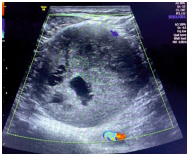

Ultrasound scan (USG) of the soft tissue using a 7-9 MHz transducer (Voluson S Pro 8 GE) of the left leg was performed which showed a 5.5 × 5.0 × 3.5 cm in the posterior aspect of the lower left thigh. The lesion was solid, homogenously hypoechoic and without any calcification. There were a few small cystic changes noted within the lesion (Figure 2). The lesion showed that arterial as well as venous flow and the lesion were separate from the surrounding bone and muscle (Figure 3). The sciatic nerve passed through the lesion.

Figure 3: USG with arterial as well as venous flow